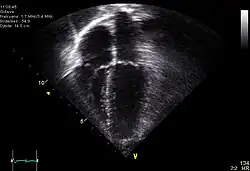

Échographie-doppler cardiaque : insuffisance mitrale.

Échographie pédiatrique.